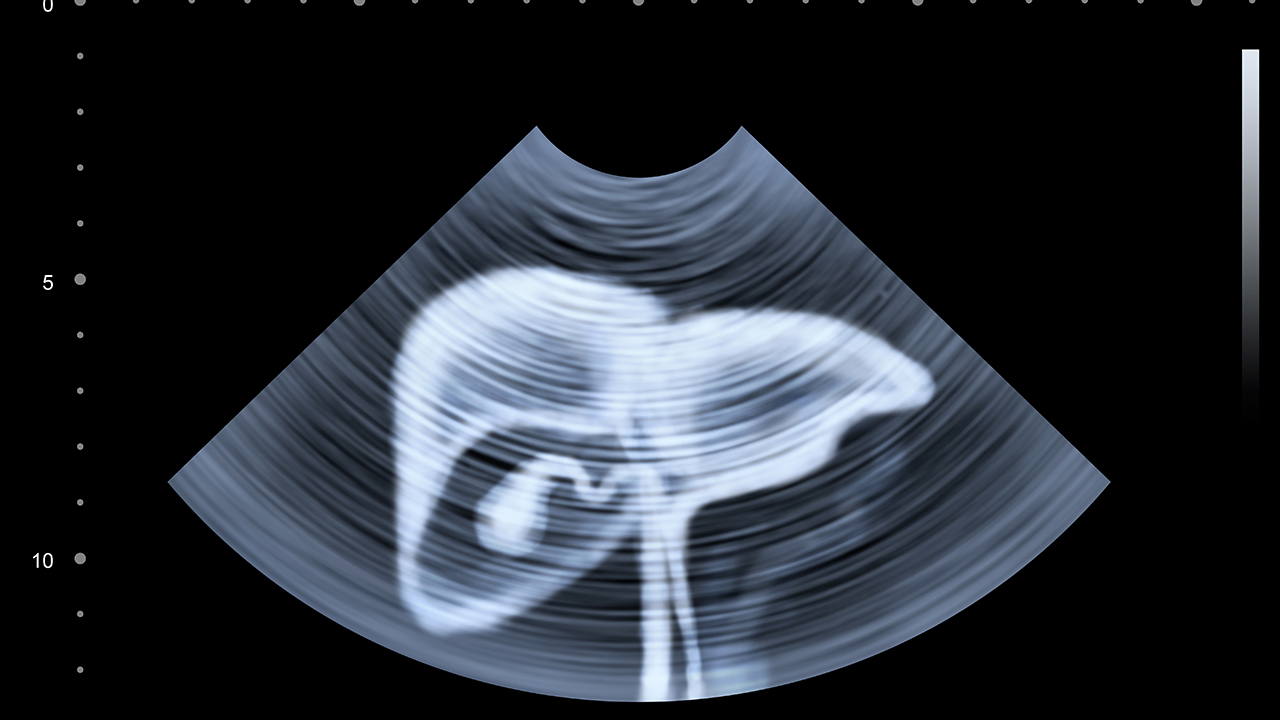

广州医科大学附属第一医院肝胆外科在肝癌诊疗方面具有较强实力。科室开展各类肝癌性手术和姑息性手术,同时注重围手术期管理和术后随访。医院拥有完善的肝癌诊疗设备,包括数字减影血管造影系统、超声引导系统等。科室重视肝癌基础与临床研究,在肝癌早期诊断标志物筛查方面取得一定成果。